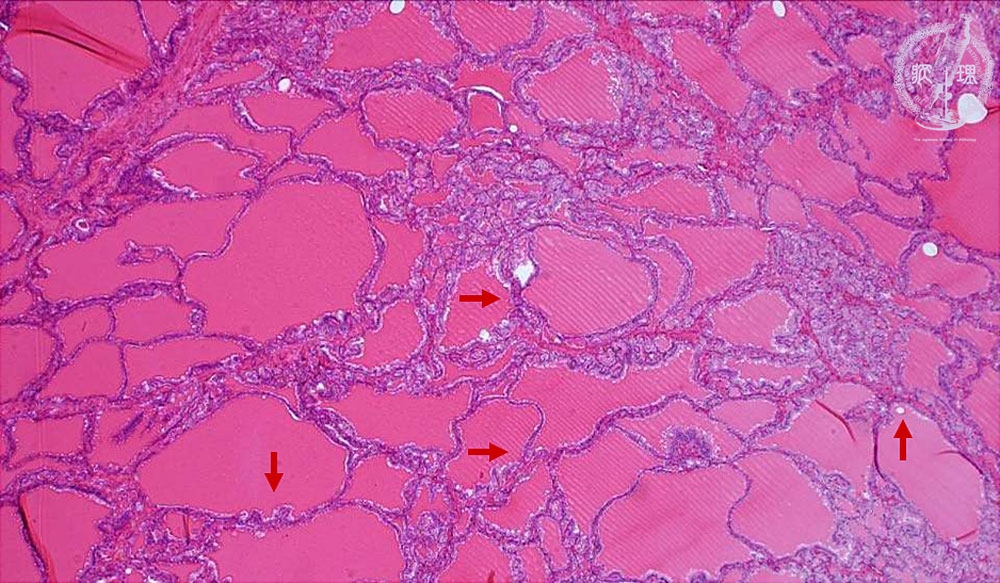

Microscopic findings (HE stain, low power view). Thyroid follicles with various sizes. A Scalloped (“moth-eaten”) appearance is apparent in the edge of the colloid.